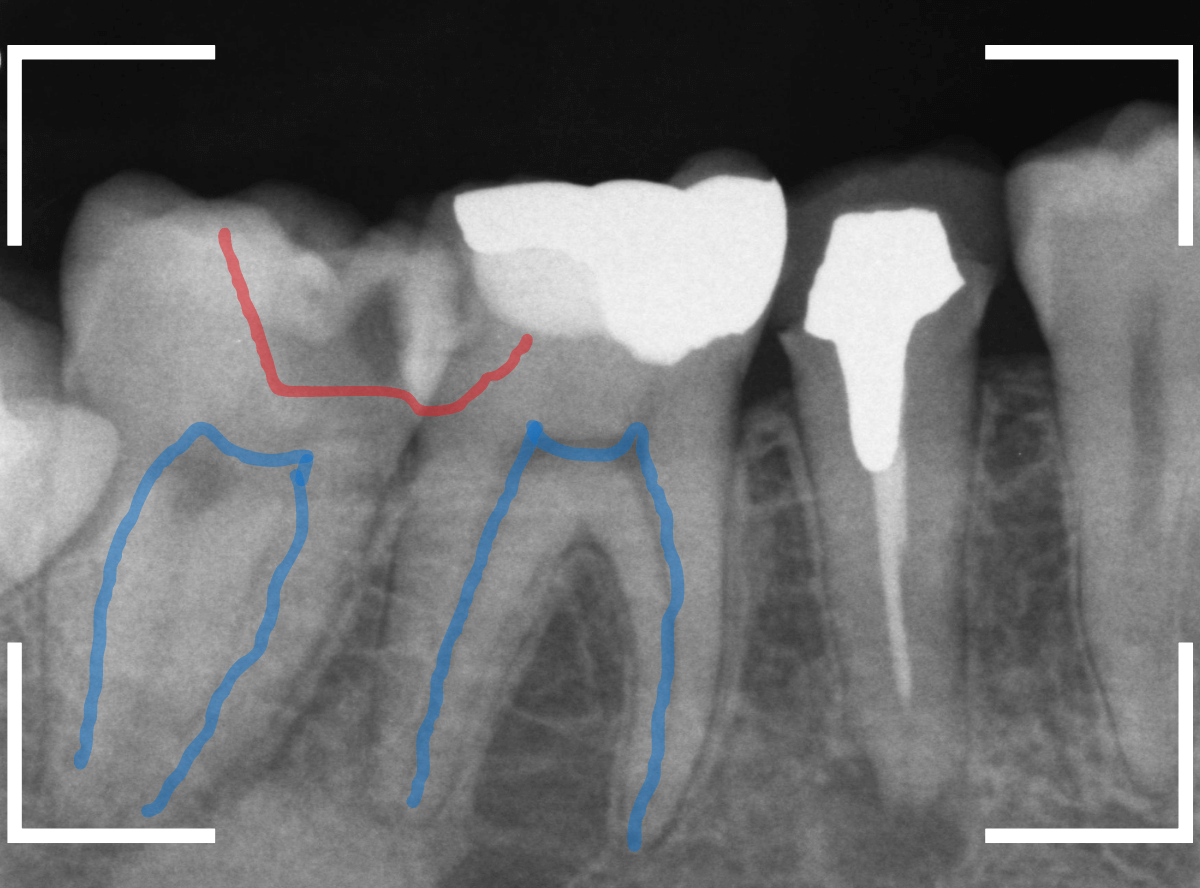

Case.24 レジンの下で虫歯が進行

上の奥歯の虫歯が見つかった患者さんです。

初診のチェックの際に、上から目視すると、レジンがつめてある〇部分が薄暗く黒くなっているので、これは虫歯があるな、とわかりました。

レントゲン写真で確認します。

赤いラインが虫歯と思われる部分、青いラインが歯の神経です。

先ほどの〇部分は明らかな虫歯になっているのがわかります。

この辺りはレジンがつめてありますが、その下もうっすらと虫歯になっていそうです。

治療を開始します。